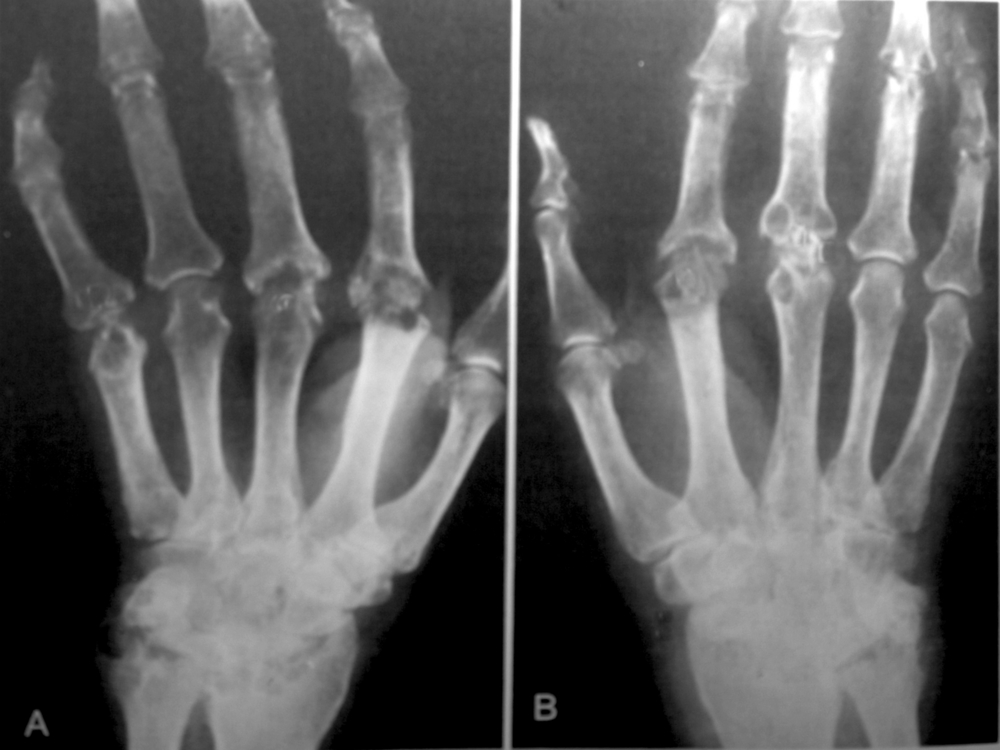

Рентгенологические изменения появляются либо в течение первого года болезни, либо по прошествии трех лет и более. На рентген-снимке можно увидеть околосуставные эрозии, т.е. «изъеденность» суставных поверхностей, подвывихи, вывихи в мелких суставах стоп, кистей.

- Существуют характерные именно для ревматоидного артрита деформации кистей – Z-образная форма, при которой сама кисть отклоняется в сторону лучевой кости, а пальцы отведены в локтевую сторону; пальцы в виде «шеи лебедя», деформация «бутоньерки». В запущенных случаях больной не может сам застегнуть одежду, обслуживать себя, брать мелкие предметы, писать.

- Пястнофаланговые суставы кистей, т.е. у основания пальцев, и средние межфаланговые страдают часто, а суставы у самых кончиков пальцев (дистальные межфаланговые) практически не поражаются.